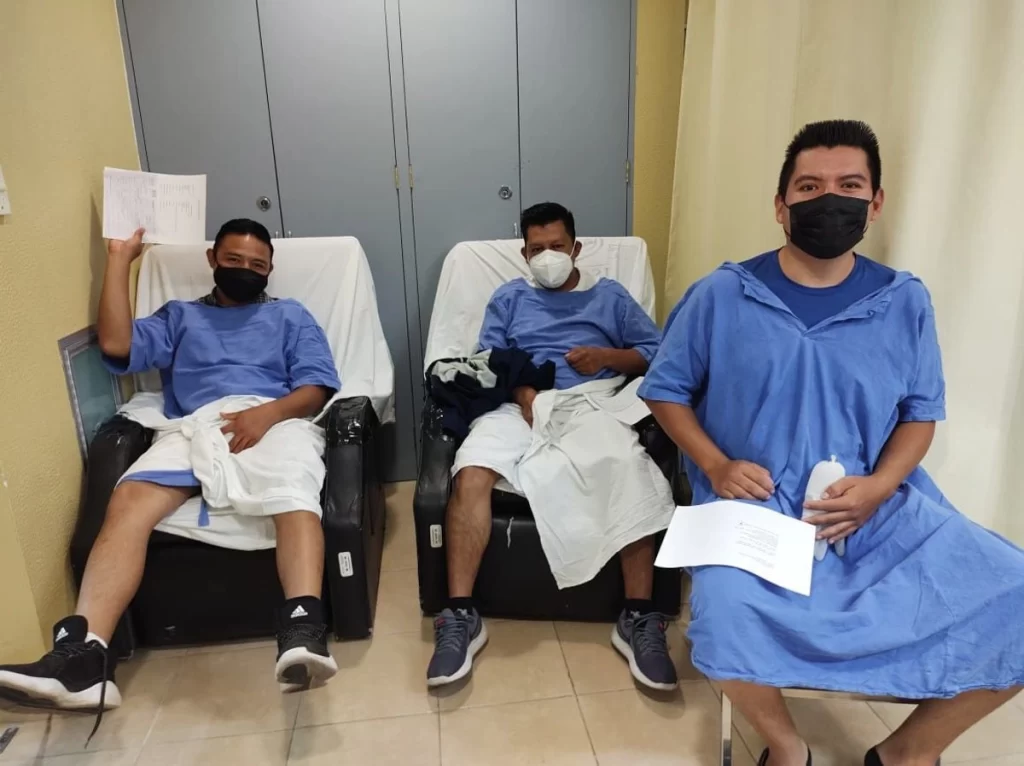

Pacientes del IMSS en Tapachula deben arrodillarse para hacer trámites; la institución revisa las ventanillas

Imágenes y videos difundidos en redes sociales el jueves 28 de mayo muestran a pacientes del Hospital General de Zona No. 1 «Nueva Frontera» del IMSS en Tapachula, Chiapas, arrodillados en el piso para poder comunicarse con el personal administrativo, entregar documentos y firmar de recibido a través de ventanillas de trámites construidas a una […]